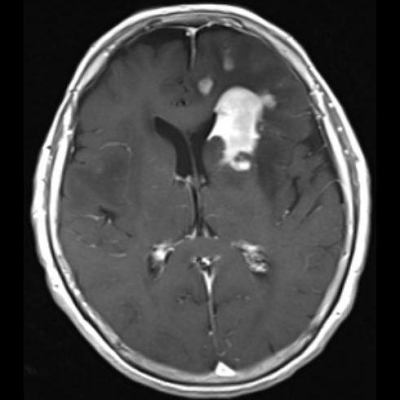

- (B) Aksiyel postkontrast T1A görüntülerde büyüğü sol frontalde kontrastlanma gösteren multipl kitle lezyonları (oklar) izlenmektedir.

- Genellikle supratentoriyal alanda, bazal ganglion, periventriküler beyaz cevher, orta hat ve korpus kallozum vb. yerleşme eğiliminde tek veya multipl kitleler şeklinde görülür.

- Kitleler çoğunlukla solid ve homojendir.

- Perfüzyon MRG’de düşük-orta düzey CBV değerleri izlenir. Lenfomalarda düşük CBV değerleri, kötü prognoz göstergesidir.